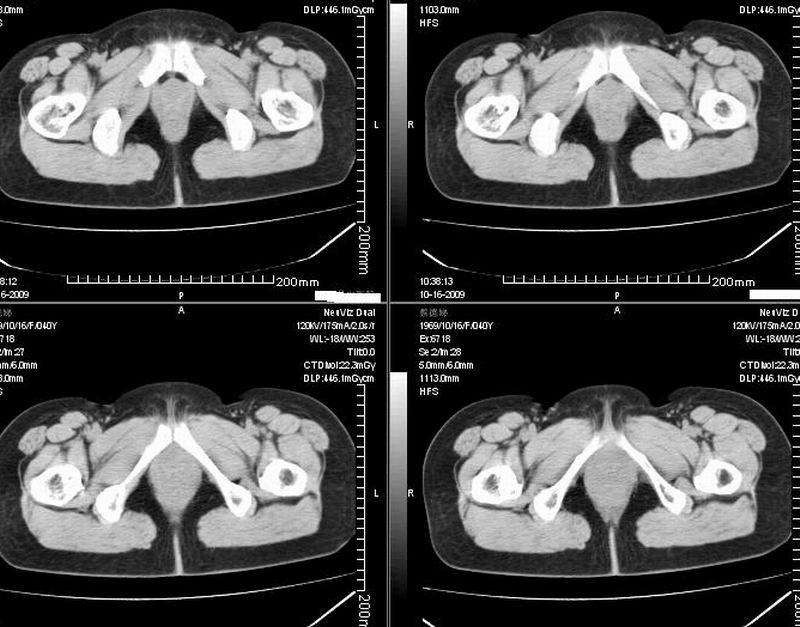

女:40y:下腹隐痛1周+,无其它不适,这个子宫会太一点吗?有临床意义吗?

宫腔内有积液,考虑炎症可能

子宫偏左,略显增大,期内可见低密度改变,考虑宫腔积液可能。

子宫偏左,略显增大,期内可见低密度改变,考虑宫腔积液可能。 不能除外肌瘤可能。

子宫体积稍增大,其内见低密度影。考虑宫腔积液可能。

子宫不规则的增大 宫腔内积液 有多种考虑

1 子宫肌瘤

2 子宫腺肌症

3 子宫内膜炎

4 月经期 (宫腔内积血)